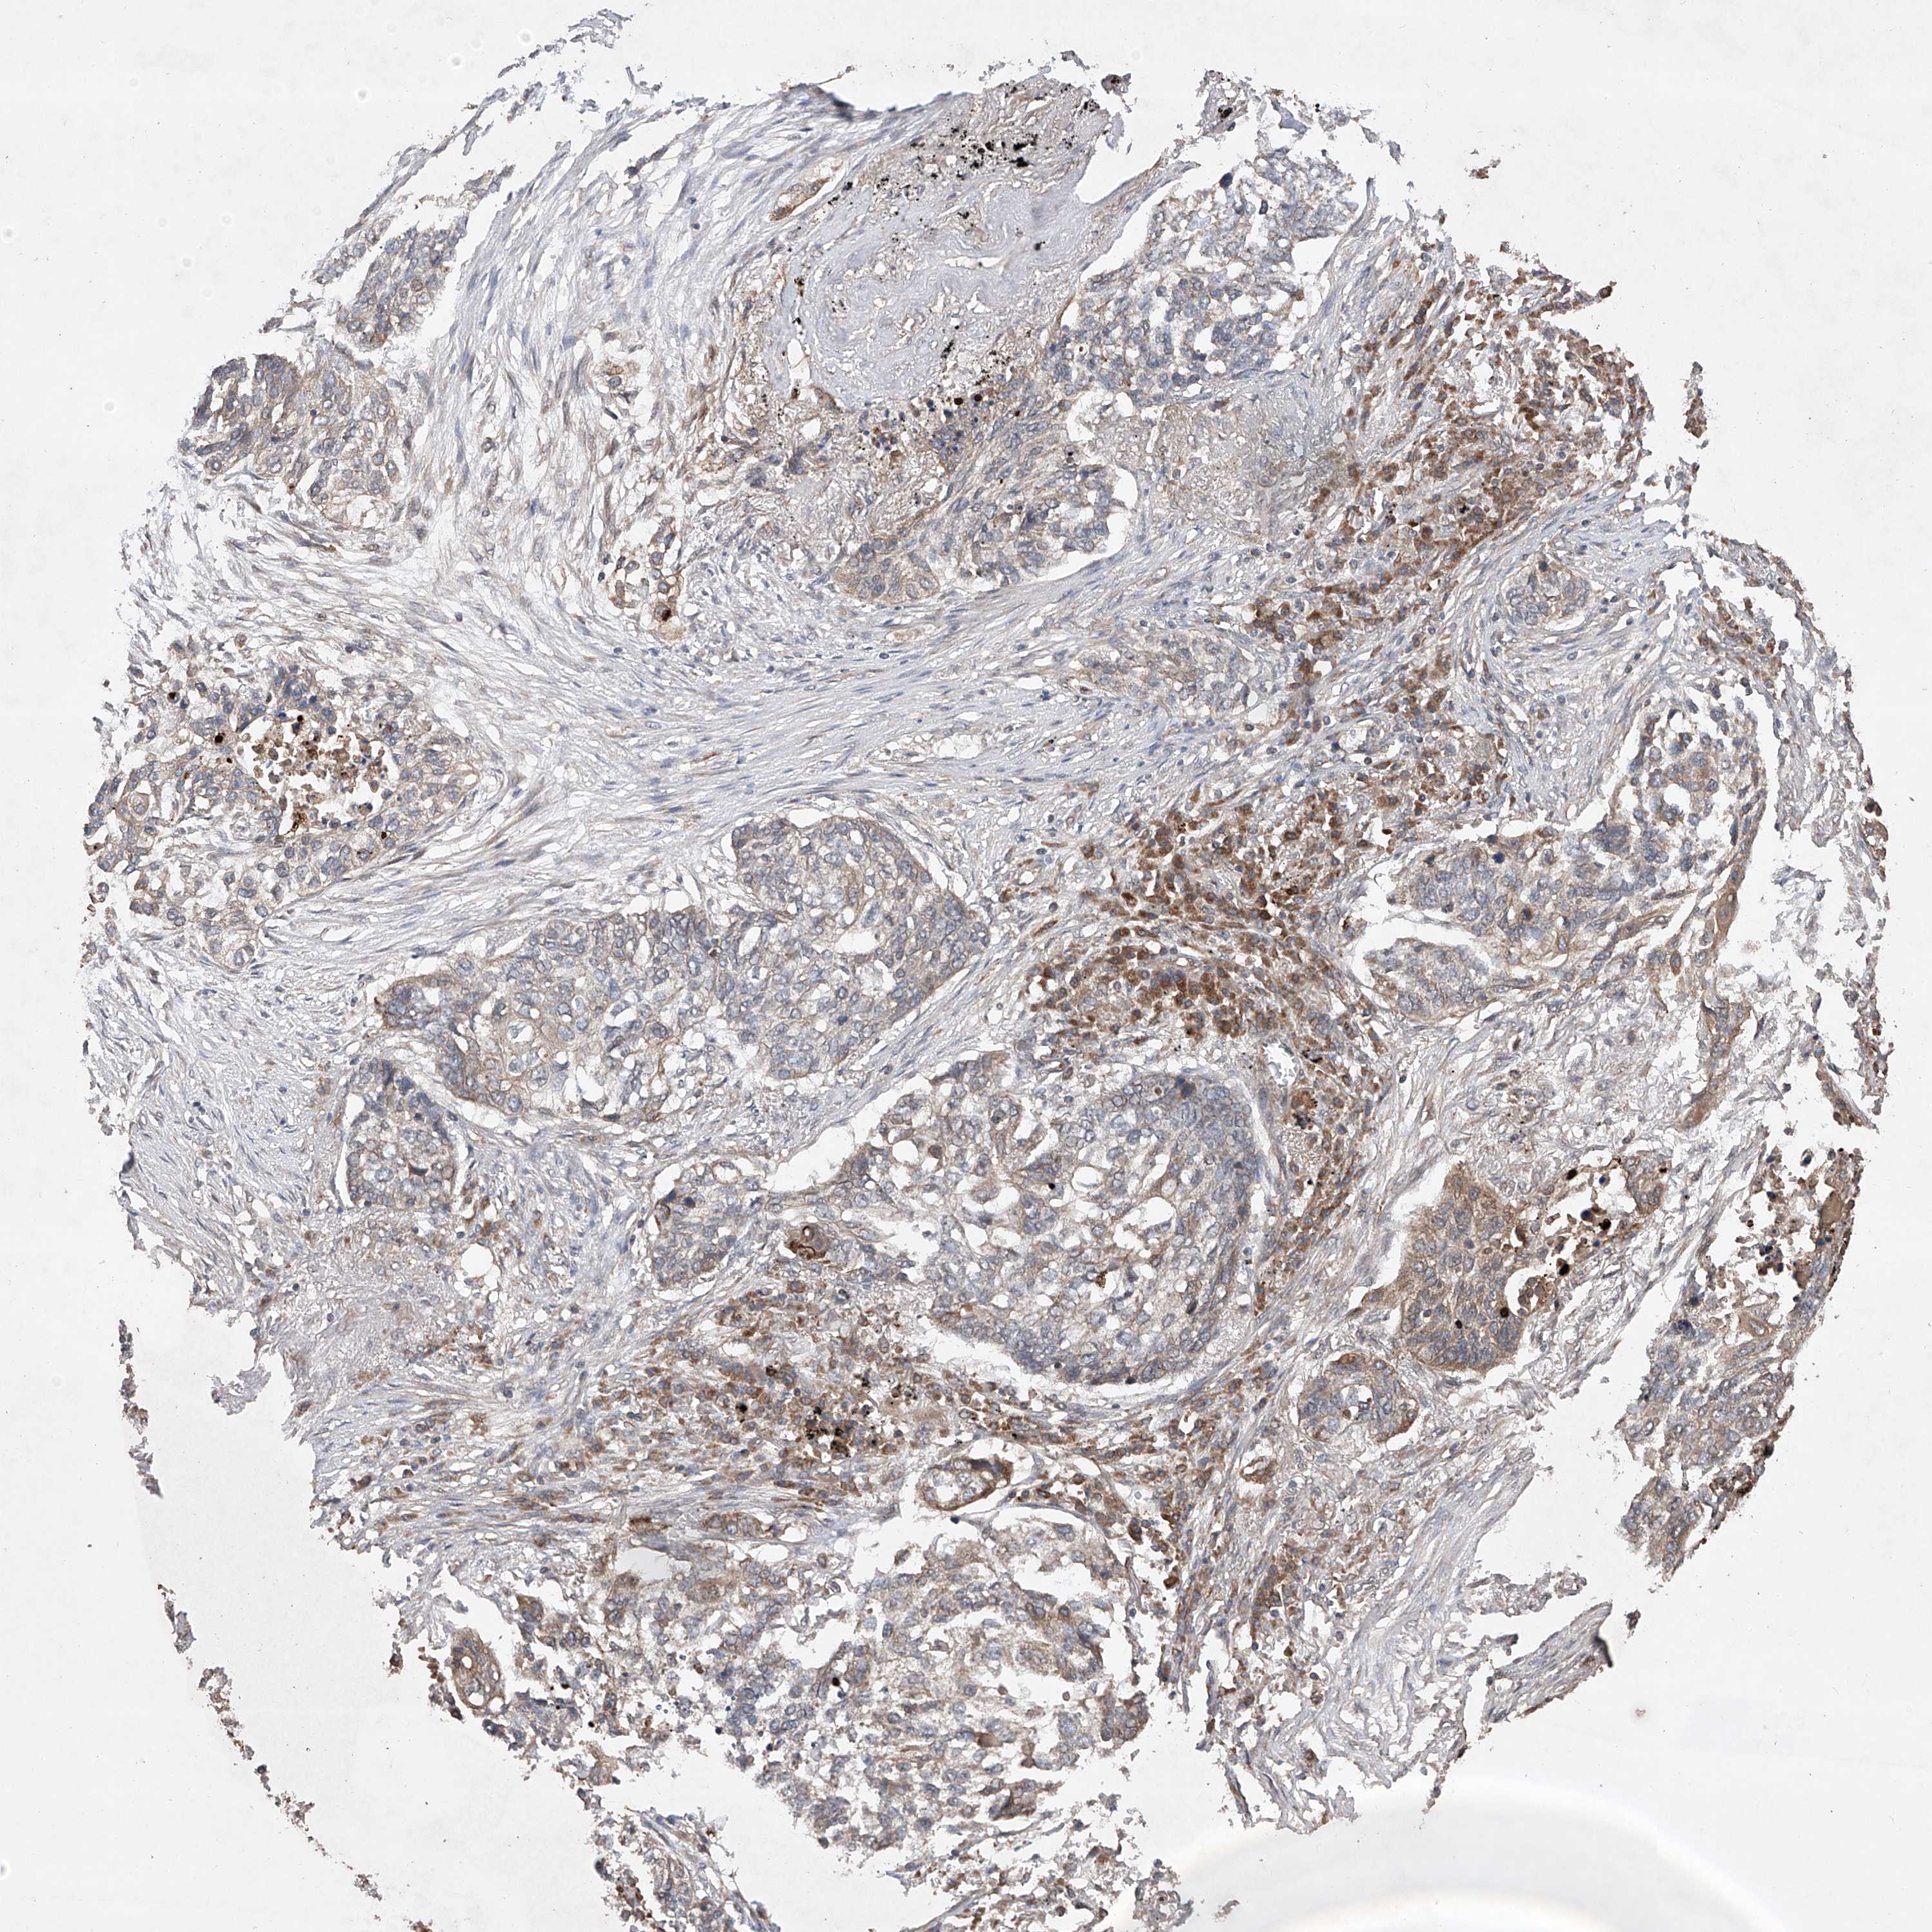

CANCER LUNG CANCER Show tissue menu

LUAD TCGA LUAD VALIDATION LUSC TCGA LUSC VALIDATION PROTEIN LUAD CPTAC PROTEIN LUSC CPTAC PROTEIN EXPRESSION

ANTIBODIES

AND

VALIDATION